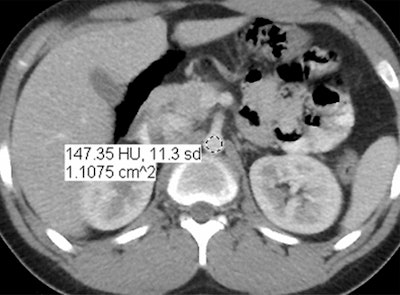

Images are of a 17-year-old boy with a history of Hodgkin's disease. Reduced-dose MBIR image (above), reduced-dose 100% ASIR image (below), reduced-dose filtered back projection image (third from top), and comparison standard-dose 30% ASIR image (bottom), all with a region of interest in the abdominal aorta for objective noise measurement. The reduced-dose MBIR image has significantly less noise compared with other reduced-dose and standard-dose reconstructions. Images republished with permission of RSNA from 10.1148/radiol.13130362, October 3, 2013.

In an objective evaluation, reduced-dose MBIR images had decreased image noise compared with standard-dose 30% ASIR images (for example, 12.7 HU versus 19.4 HU in the aorta, respectively, and 8.7 HU versus 14.2 HU in the liver).